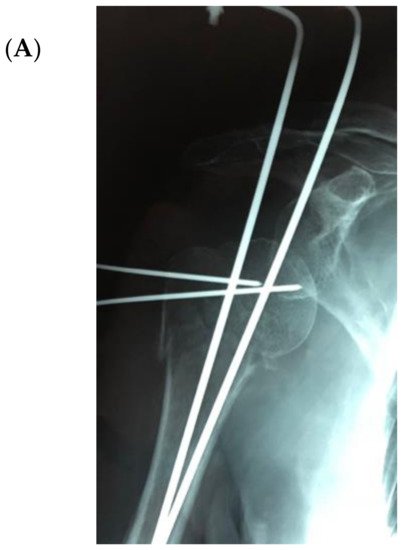

The bone substitute GlassBONE Putty (Noraker, Villeurbanne, France), made of bioactive glass, was routinely employed in revision surgeries requiring bone loss filling in our surgeries. This ceramic is composed of Silicium, Calcium, Sodium and Phosphorous, minerals which are naturally present in the human body; it is in a ready-to-use format and can be injected through the syringe (Figure 1): it may be used both to increase prosthesis-bone interface stability and fill bone defects in PJIS revision surgeries, also contributing to preventing re-infection. In this regard, a peculiar case was reported (Figure 2): infection after percutaneous treatment of a proximal humerus fracture. The pinning removal and the implant of a cement antibiotic spacer were attempted. Finally, an RSA (Equinoxe Shoulder System, Exactech Inc., Bloomington, MN, USA) was implanted with the addiction of bioactive glass to prevent tuberosity defect augmentation and re-infection.

Figure 2.

An infection after percutaneous pinning of a proximal humerus fracture. (A) Preoperative X-ray. (B) The subsequent implanting of a cement antibiotic spacer (red circle underlines bone loss); (C) the final reverse arthroplasty (RSA) with the addition of bioactive glass in the tuberosity defect.